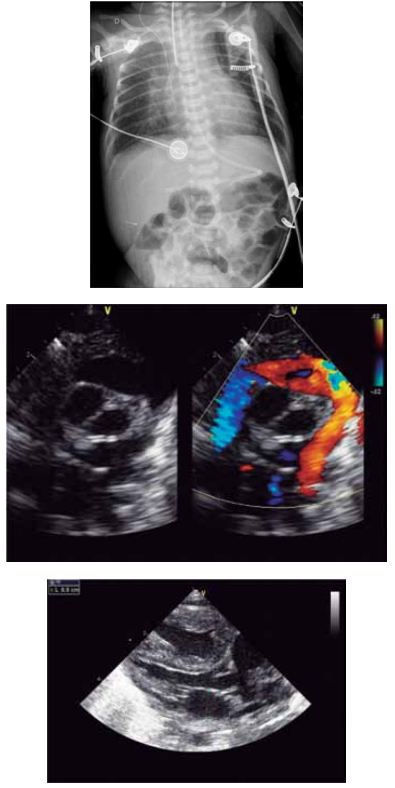

Paciente de 1 ano e 1 mês veio encaminhada, via

CROSS, por cardiopatia congênita. A avó refere que a

criança, desde os 2 meses de idade, fica com a boca roxa

quando chora. Lembra de ter levado a uma UPA, sendo

auscultado um sopro na ocasião e aferida saturação periférica de oxigênio em ar ambiente de 98%. Avó refere,

também, sudorese importante e cansaço às mamadas

com dificuldade de ganho pondo-estatural, além de infecções respiratórias frequentes.

(Arquivo pessoal; imagens usadas com autorização)

Diante do exposto, o diagnóstico correto é: